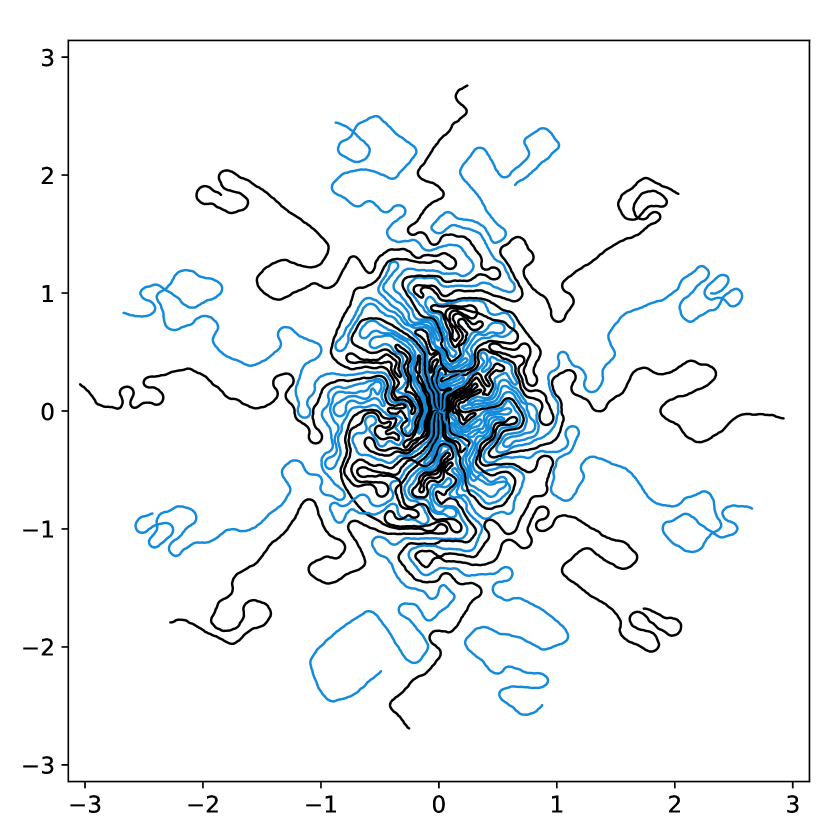

A natural approach to solve (6) is to optimize the coefficients using a gradient based algorithm. Indeed, one may hope that the reparameterization of the cost function with a density prevents the appearance of spurious minimizers described in Gossard et al. (2022). Unfortunately, this is not the case and gradient based algorithms might be trapped in such local minimizers. Fig. 4 and 5 illustrate this fact. In Fig. 4, the baseline sampling scheme is shifted continuously in the and directions. The cost function is evaluated for each shift and displayed in the right. Observe that many local minimizers are present. Similarly, in Fig. 5, a target density is varied continuously in a subspace consisting of eigen-elements . Again, the energy profiles on the right are highly oscillatory.

Overall, this experiment shows that the gradient direction is not meaningful: it oscillates in an erratic way. This advocates for the use of 0th order optimization methods. A significant advantage of this observation is that it allows discarding the memory and time issues related to automatic differentiation.

images.

images.